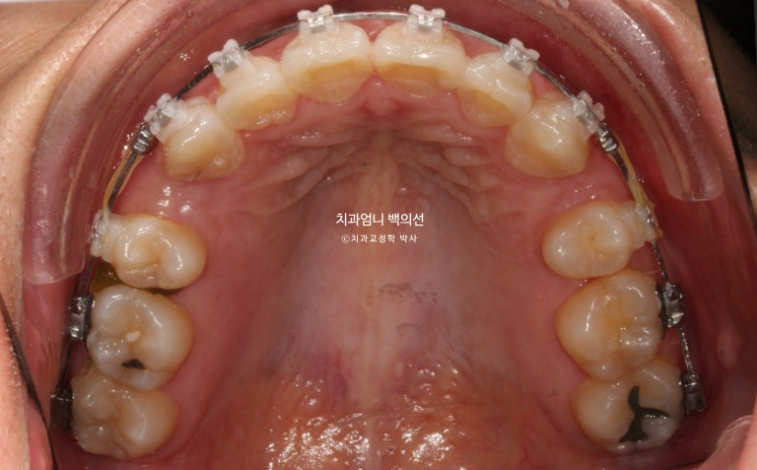

24.07

치료시작 10개월째 모습입니다.

상악 발치공간이 보입니다.

아래는 송곳니를 앞니자리로 끌어오는 중입니다.

환자분이 30대임에도 치아이동속도가 빠른 편이였고